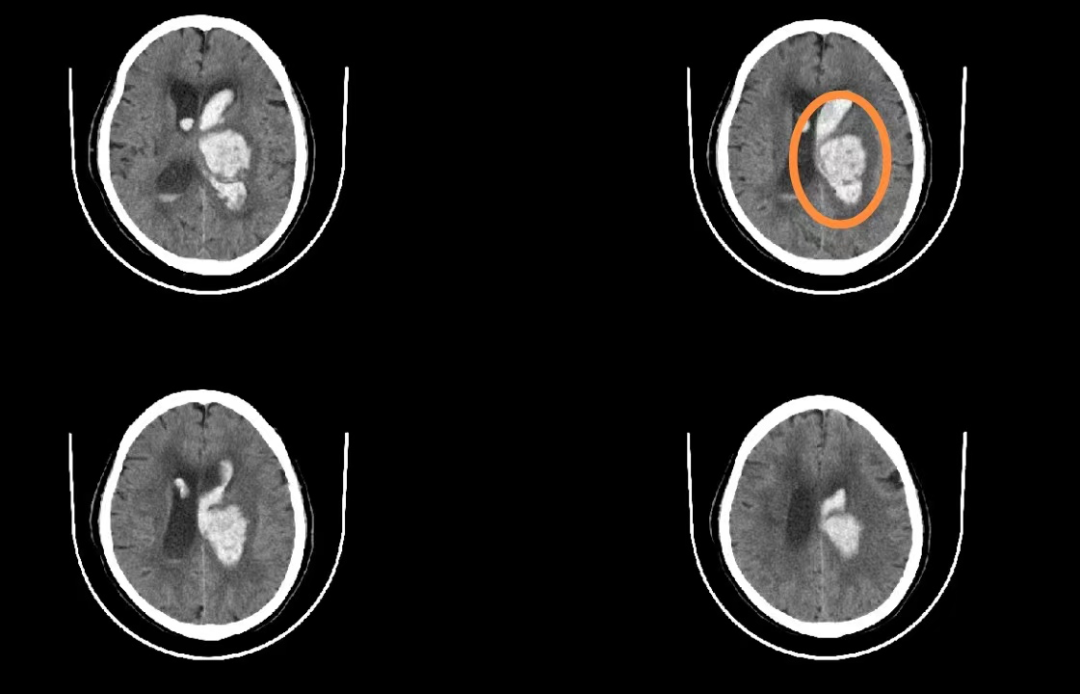

患者的CT檢查結果

42歲的劉先生突然出現右側肢體無力,伴有明顯頭痛、嘔吐等癥狀,被家人緊急送至惠州三院急診科,行頭顱CT檢查提示腦出血。神經外科團隊給予及時施行神經內鏡下腦內血腫清除手術后,患者才轉危為安,保住了生命。